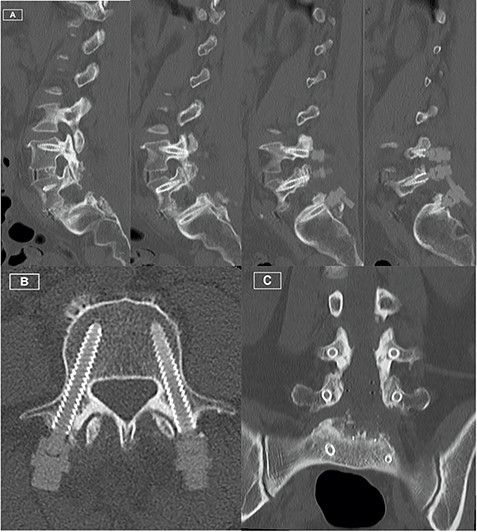

The patient recovered well, with resolution of her lower limb radiculopathy. Ongoing low back pain was managed by a multidisciplinary pain team. At 6 months post-operative, the patient experienced some recurrence of right leg pain. CT revealed excellent hardware position with no pseudarthrosis. MRI demonstrated adequate decompression of the descending and exiting L5 nerve roots, with minor perineural thickening within the right L5/S1 foramen. This patient was managed conservatively for her pain, given the lack of radiological pathology identified on CT and MRI. Figures 1–3 highlight the low artefact presence on both post-operative MRI and CT, allowing for optimal assessment of bony and neurological structures.

Postoperative CT Lumbar spine. (A) Sequence of sagittal slices demonstrating excellent definition of screw trajectory. (B) Axial slice through L4 pedicles demonstrating definition of screws and distinction from bony cortex. (C) Coronal slice demonstrating screws at all levels with no peri-structural artifact.